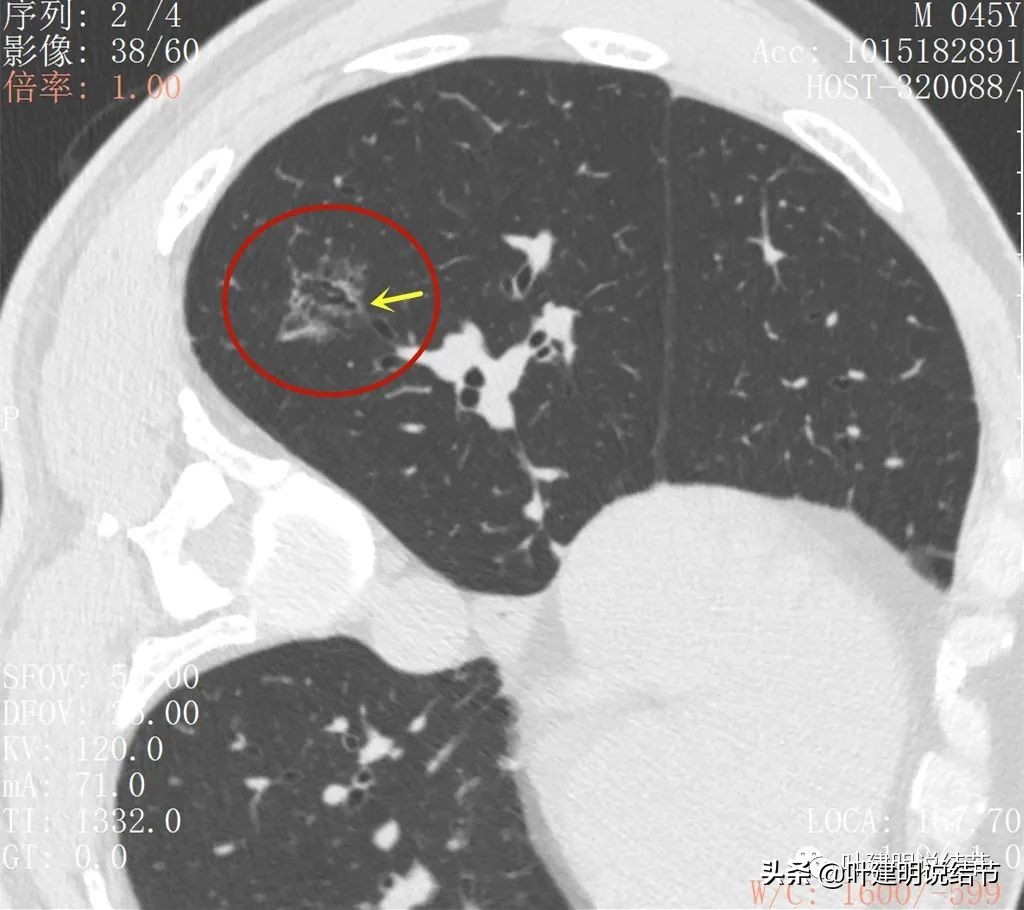

再来看薄层扫描:

病灶感觉很散在,但内部有扩张的细支气管(黄色箭头)、边缘略显不清(绿色箭头),部分有偏实性(粉色箭头)。